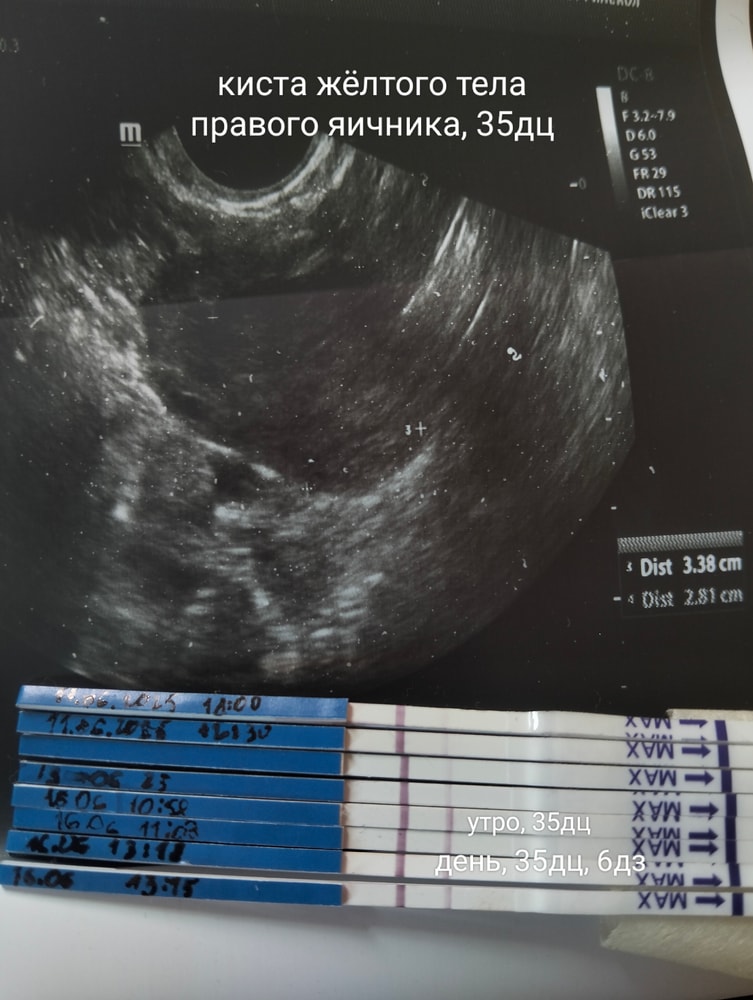

Киста жёлтого тела, 6дз, 35дц.

УЗИ

Сегодняшнее УЗИ и тесты, которые делала с первого дня задержки. Сегодня внезапно поярчали полоски.

Жду завтра утром результаты ХГЧ крови.

Боюсь внематочной беременности, не знаю, как не опоздать с этим. Только по динамике хгч.

Шла на УЗИ сегодня по поводу болей(тянет справа и внизу, как при месячных, со спазмами, а месячных нет.